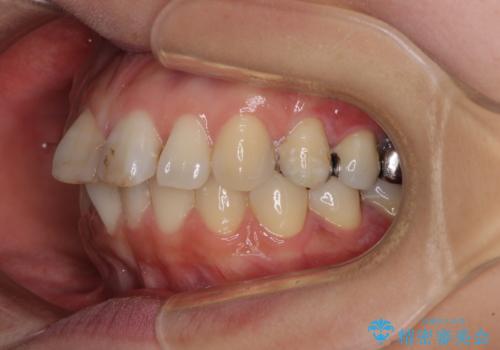

- 前歯のデコボコを治したいとのことで来院された患者様です。

上下顎ともに歯列全体の後方移動とIPR(歯と歯の間を削る)によってデコボコが解消するように設計し、インビザラインにより治療を行うこととしました。

しっかりと装着時間を守ってくださったのですが、途中妊娠にともなう悪阻や出産といったイベントがあり、予定よりも治療期間が長くなりました。